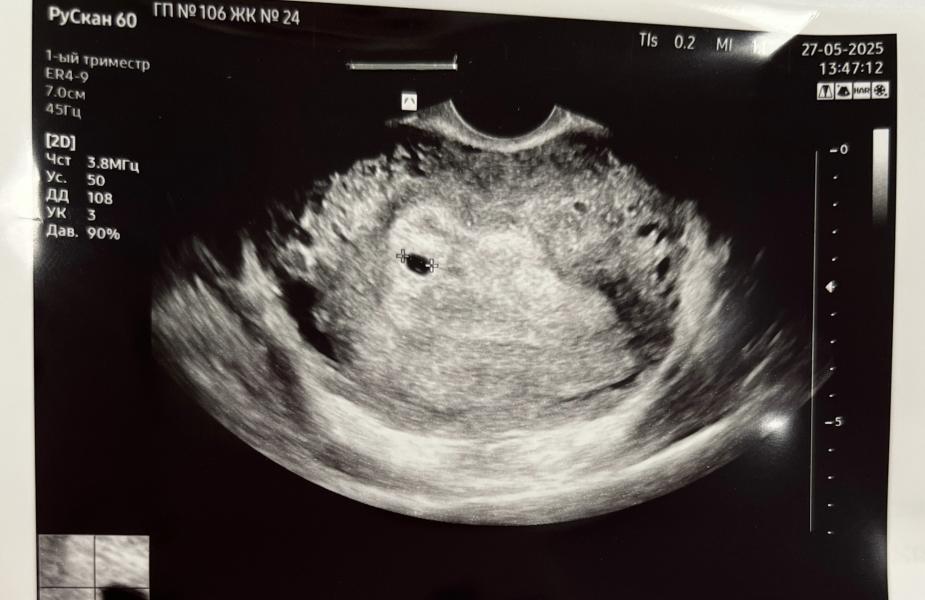

18дпо срок 5 недель.

На узи нашли плодное яйцо с одним живым эмбрионом 3 мм

ВДПЯ 15,2мм

Желточный мешочек 3,6мм

Контроль узи 9.06 🥹